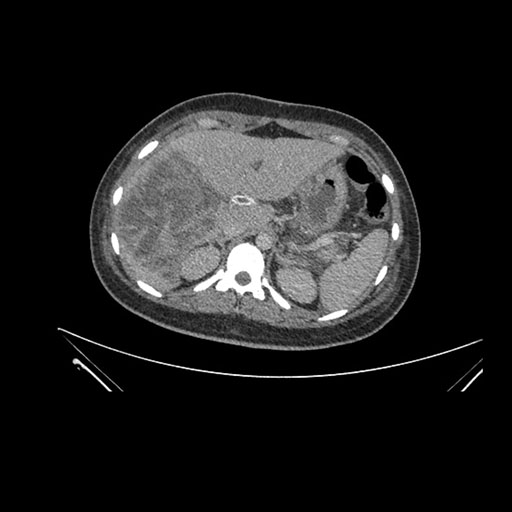

Imaging Analysis

Look through the patient's CT scan to identify any areas of concern for the necessary procedure.

Coronal Arterial

Based on initial findings, which issue(s) would you be most concerned about?